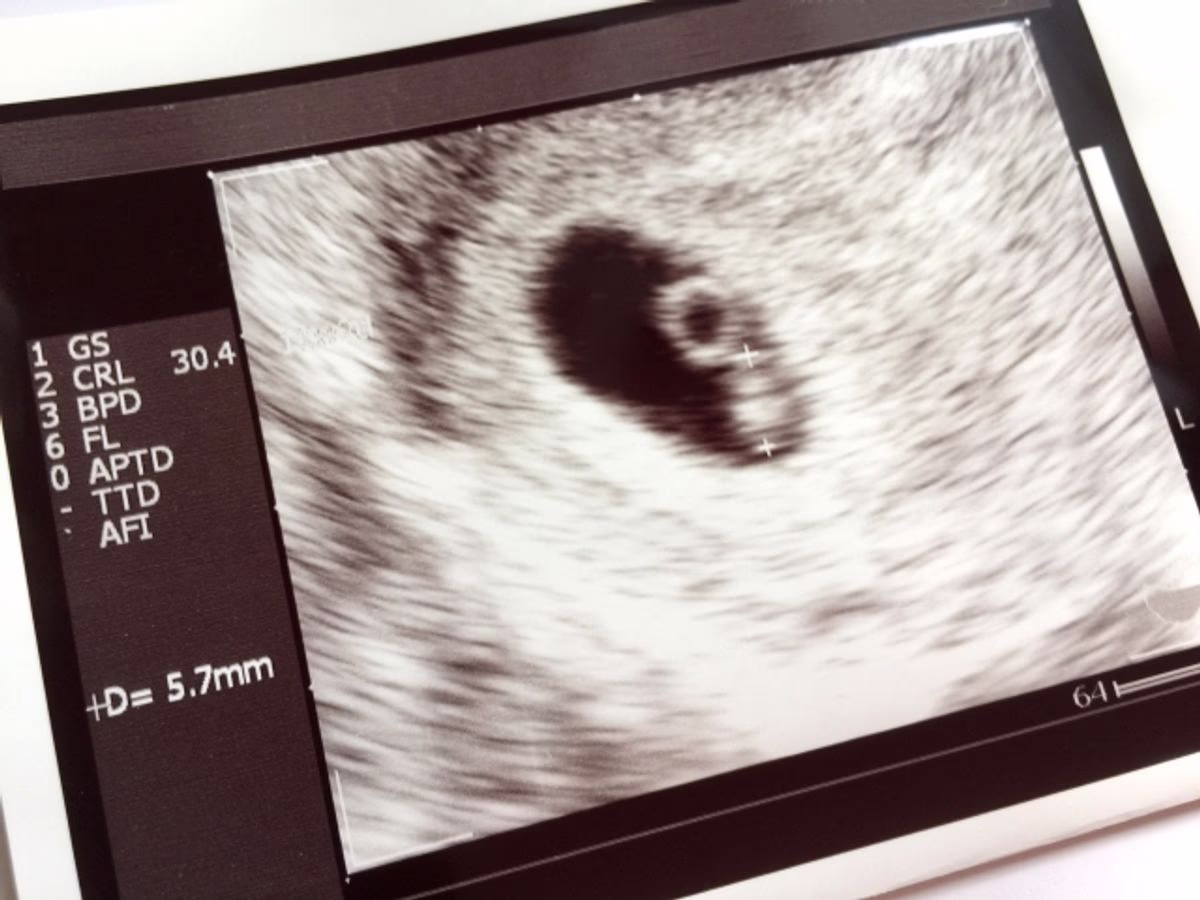

胎児スクリーニング検査には色々な種類がありますが、一般的に「胎児スクリーニング」というと「胎児超音波スクリーニング検査」のことを指し、超音波(エコー)を使ってお腹の中の赤ちゃんのカラダや臓器のつくりに異常がないかを確認していきます。

この胎児超音波スクリーニング検査は「胎児ドック」と呼ばれることもあります。

超音波検査は通常の妊婦健診でも行い、お腹の中の赤ちゃんの様子を確認します。

妊婦健診で行う超音波検査と胎児超音波スクリーニング検査の違いを解説します。

妊婦健診で行う超音波検査の目的は、赤ちゃんが週数に応じた発育をしているかを確認することです。

検査は妊婦健診を担当している産婦人科の医師が行います。頻度や回数は、厚生労働省から示されている検査時期の目安に沿って病院やクリニックで決められていたり、ママとお腹の中の赤ちゃんの発育の状態によって医師が決めたりします。

胎児超音波スクリーニング検査の目的は、赤ちゃんに形態的(カラダのつくりや臓器など)に異常がないかを確認することです。

専門のトレーニングを受けた医師や検査技師が、長時間かけて超音波でお腹の中の赤ちゃんのカラダをじっくりとみていきます。

どの病院でもできるというわけではなく、実施している病院やクリニックは限られます。

胎児超音波スクリーニング検査は自費診療となり、費用は病院やクリニックによって異なります。